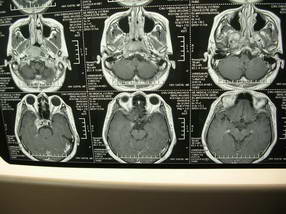

扫描示鼻咽腔不对称,中度狭窄,右侧咽隐窝消失,局部软组织肿块,鼻咽右侧壁增厚形成肿块,突入鼻咽腔,肿块平扫呈等密度,肿块向深部侵润,右侧翼内外肌受侵,右侧咽旁间隙变窄;向后生长,头长肌界线欠清,向后上生长侵犯同侧颈动脉鞘区。双侧海绵窦增宽,内见软组织影与鼻咽部肿块相连。考虑鼻咽癌。鼻咽癌主要是放射治疗,且效果较好;到当地有治疗设备较大医院治疗即可。

鼻咽部新生物(纤维血管瘤?鼻咽癌?)侵犯右侧中颅窝底及右侧海绵窦;建议必要时活检定性。

鼻咽部新生物侵犯右侧中颅窝底及右侧海绵窦,鼻咽癌可能性大。建议增强扫描。纤维血管瘤禁忌穿刺。